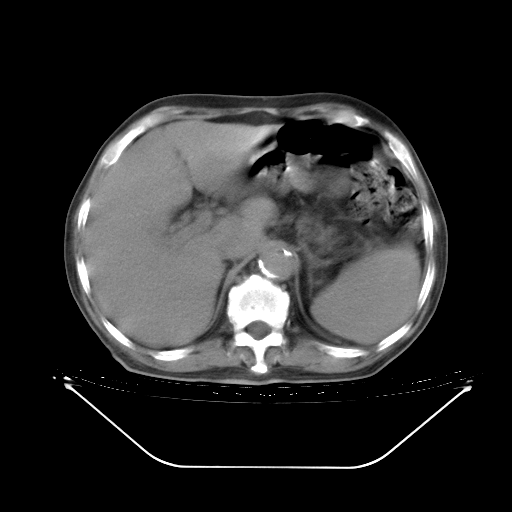

今天复查肺部CT,发现双肺广泛磨玻璃样改变。所以我把3月19日和5月9日相隔50天的肺部CT上传。请大家会诊。

2009年3月19日肺部CT片。

5月9日肺部CT(在4月27日齐鲁医院肺部CT描述部分肺组织磨玻璃样改变,12天后肺组织广泛磨玻璃样改变)